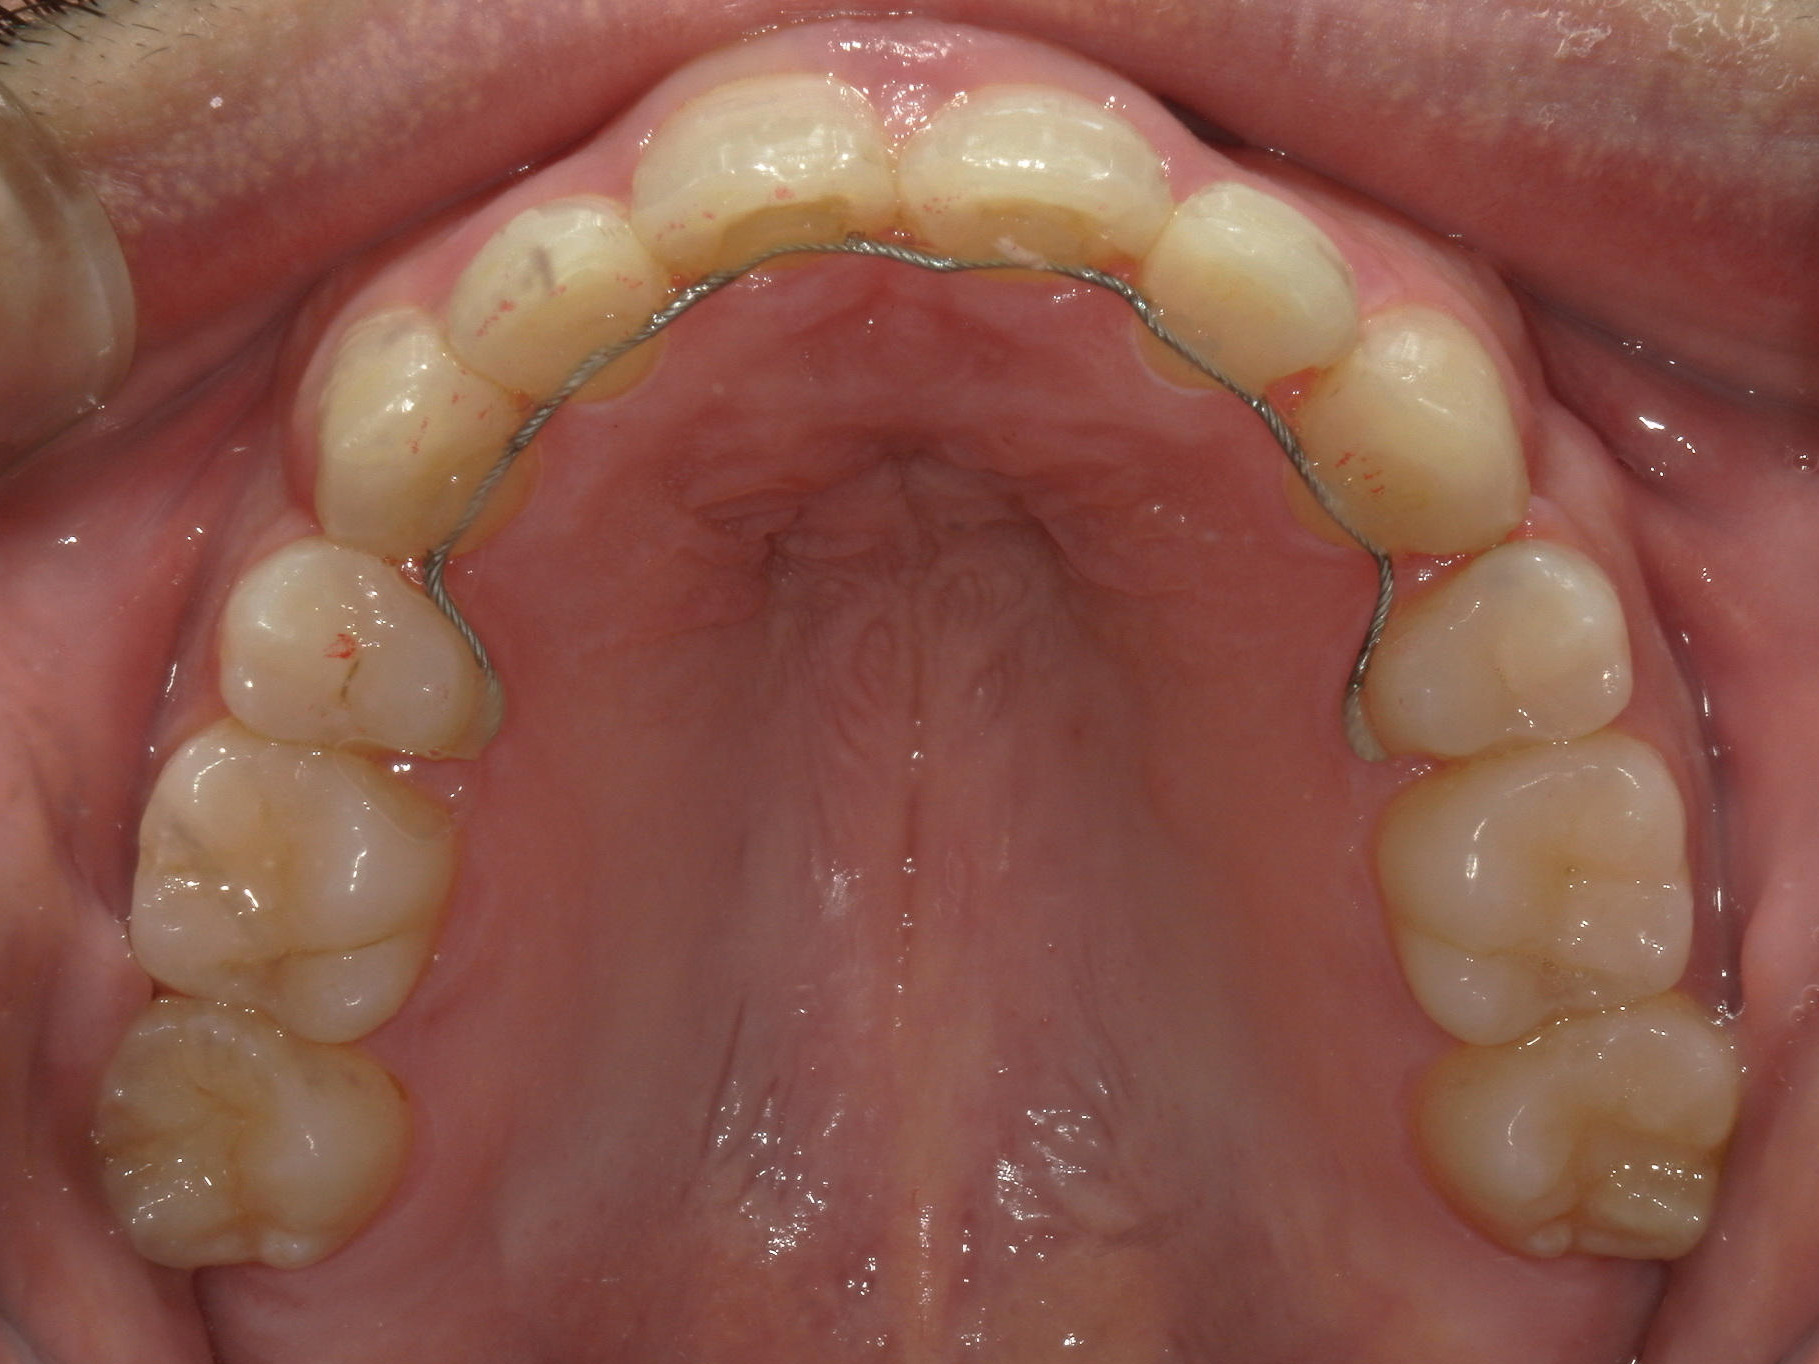

全顎ワイヤー矯正 症例(79)

主訴: 前歯が噛み合わない。歯並びが気になる。

ミニインプラント、アップライトスプリングを併用。

カテゴリー : ガタガタ(叢生) , 噛み合わせが深い(過蓋咬合)